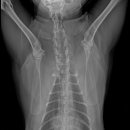

• 24시 에피소드 동물 메디컬 센터 | 만촌동 동물병원 강아지 요골·척골 골절 수술 후기 [24시에피소드동물메디컬센터]

만촌동 동물병원 강아지 요골·척골 골절 수술 후기 [24시에피소드동물메디컬센터] 만촌동 동물병원 ​ 안녕하세요. ​ 풍부한 경험과 따듯한 진료를 바탕으로, 반려동물의 건강하고 행복한 하루하루를 함께 만들어 가는 만촌동 동물병원 24시에피소드동물메디컬센터 입니다. 24시에피소드동물메디컬센터 대구광역시 동구...

에피소드동물메디컬센터(2025-06-26 12:41:00)